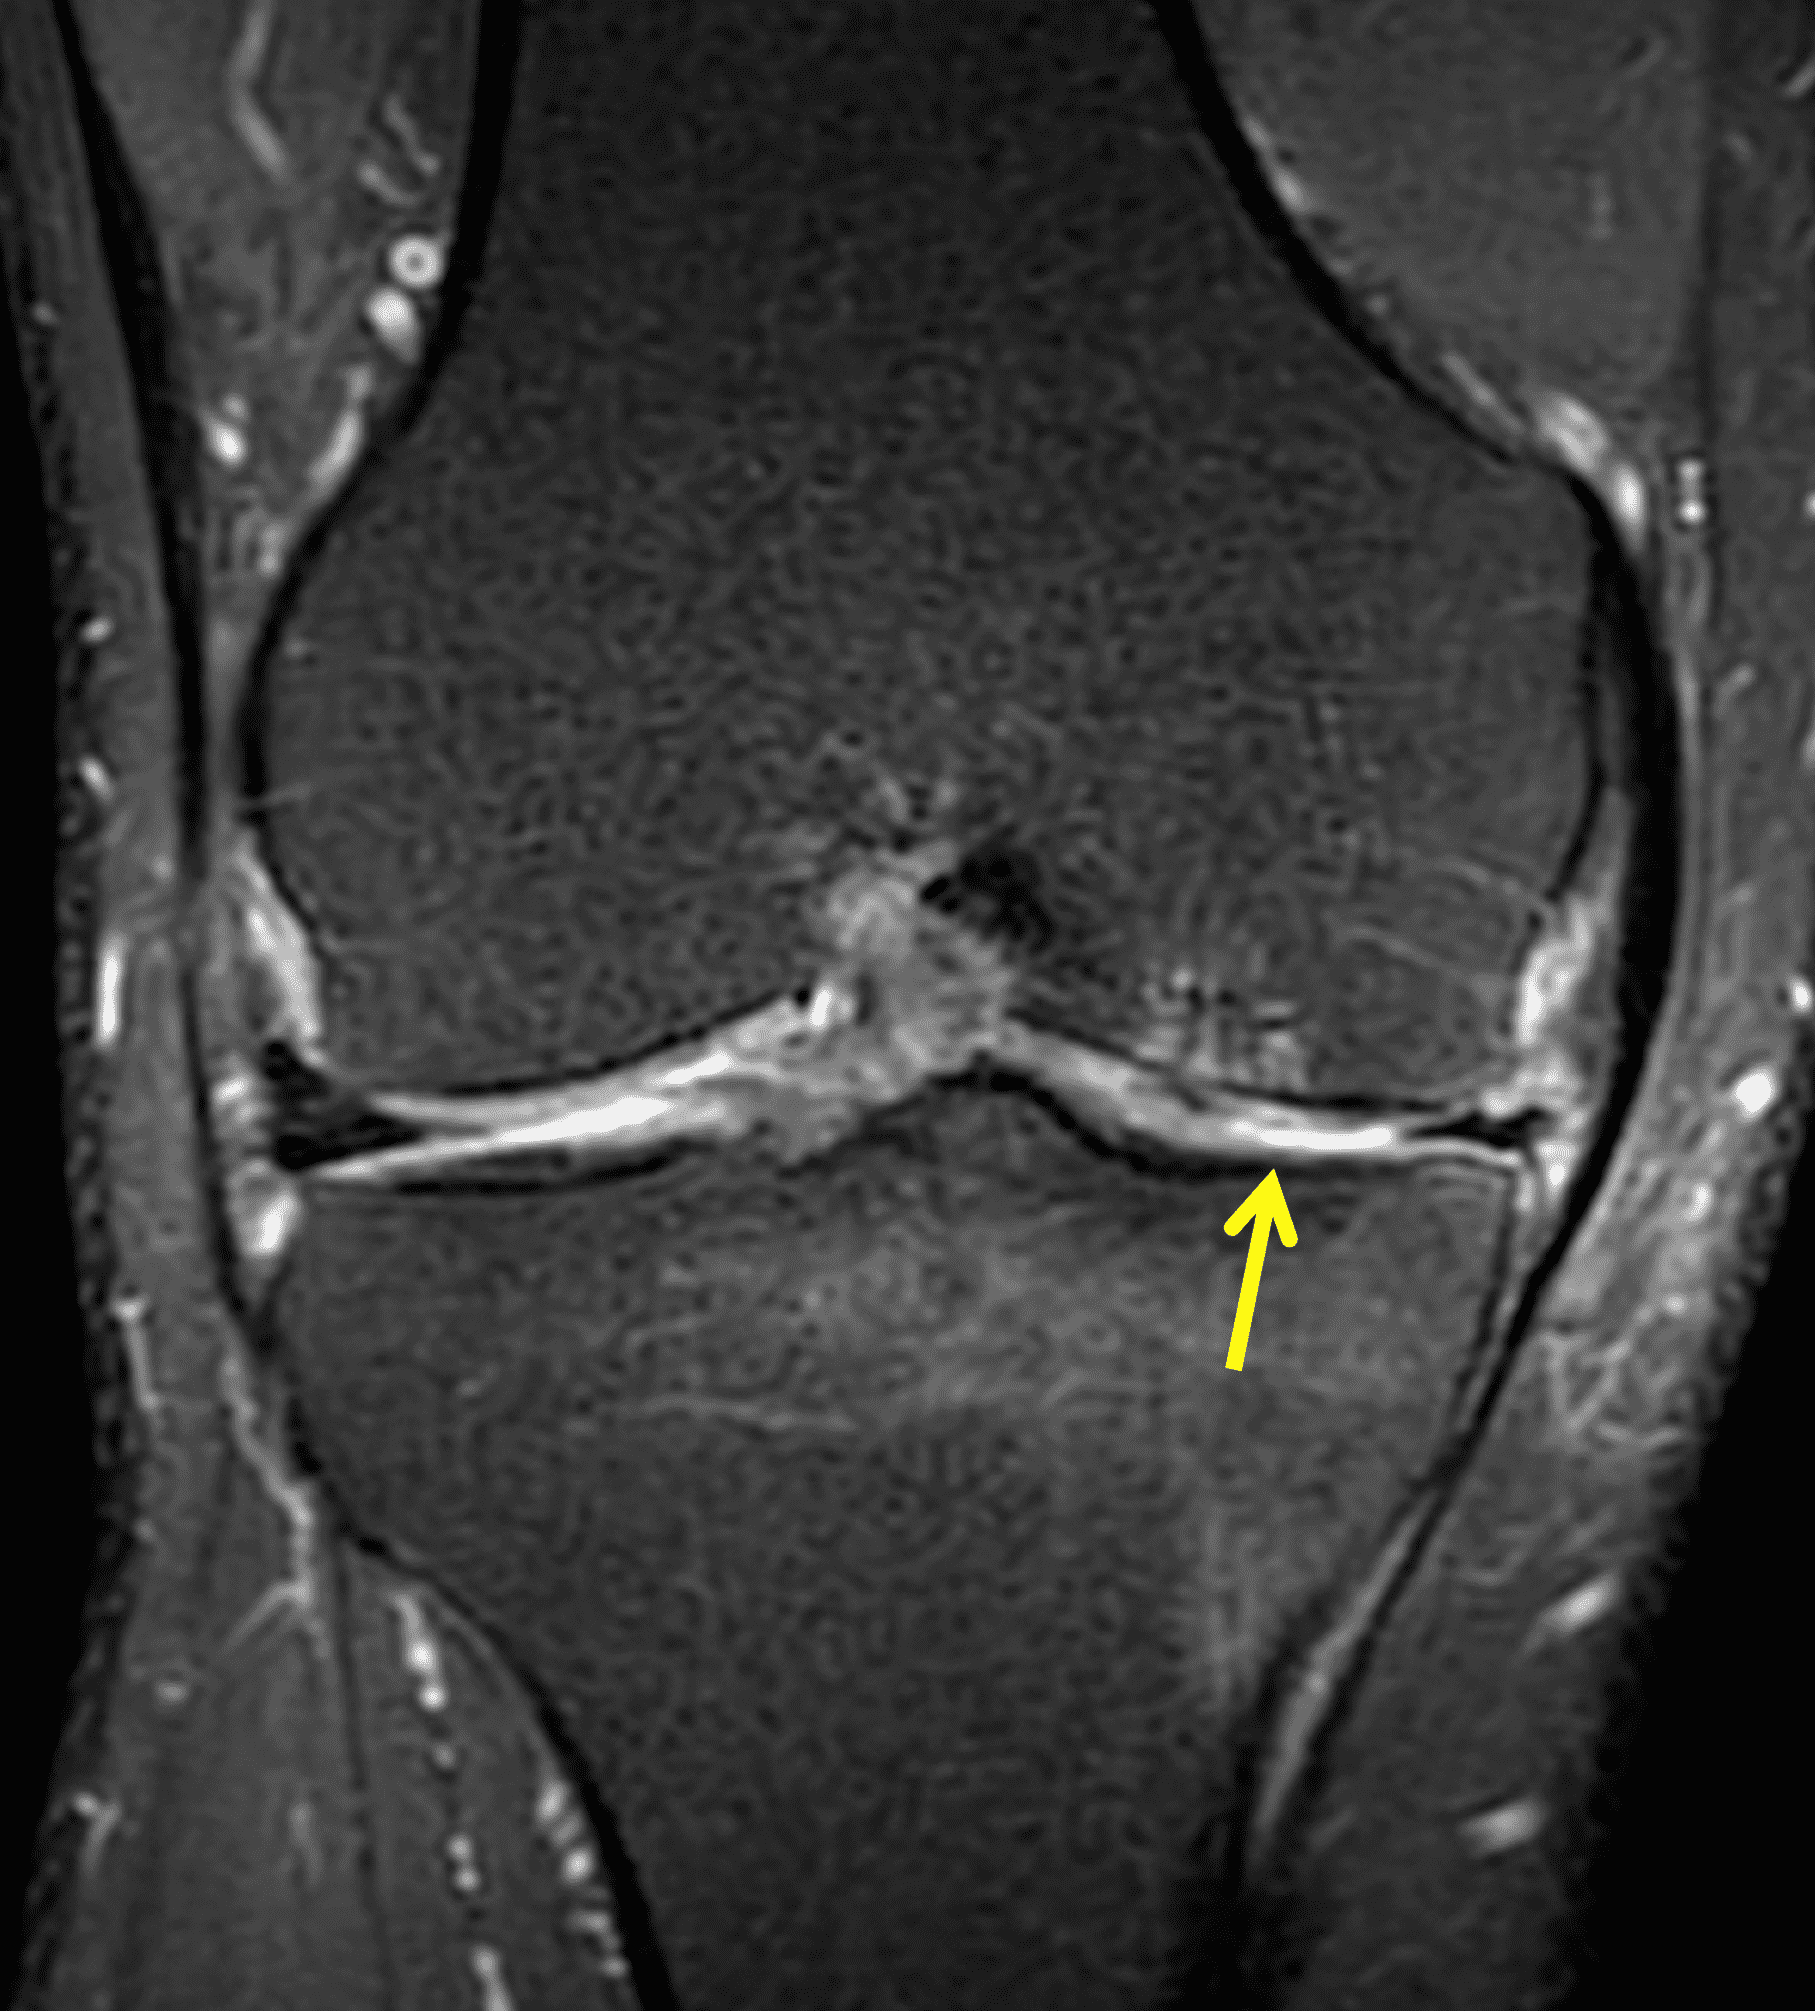

A 32-year-old man suffered a traumatic chondral injury to the medial femoral condyle that was treated with an osteochondral allograft 20 months previously. Representative images from a current knee MRI include (1A) coronal fat-suppressed fluid-sensitive and sagittal (1B) T1-weighted, (1C) proton density-weighted, and (1D) T2-weighted sequences. Are the post-operative MRI findings normal and expected, or abnormal and pathologic? Based on these images, would you characterize the procedure as a success or failure?

Figure 2: (2A) On the coronal image, the margins of the osteochondral graft are faintly visible (arrowheads). Both the graft and underlying bone show mild marrow edema, an expected finding. (2B) The T1-weighted image shows continuity of the marrow in the graft (asterisks) with the underlying bone, indicating osseous integration. A bioabsorbable pin (arrow) used for graft fixation is partly visible. (2C) The proton density-weighted image shows a low signal intensity seam (black arrow) between the native cartilage and transplant, as well as a defect in the subchondral bone plate of the graft (red arrow) where the pin was drilled, both normal findings. (2D) The T2-weighted image shows a smooth, congruent articular surface (arrows), restoring the normal anatomy, and a tiny subchondral cyst. No findings are present to suggest graft failure. The patient’s current symptoms were attributed to pathology elsewhere in the joint (not shown).

Successful osteochondral allograft procedure.

The postoperative imaging appearance of osteochondral allografts is similar to autografts (Figure 2).33 The subchondral bone plate of the donor and recipient sites do not have to match, but the articular surface should be congruent. Grafts that fail to incorporate by one year have a poor prognosis. Persistent marrow edema (beyond 12 months), a thick graft interface containing cysts or fluid, and subsidence of the graft are associated with poor osseous healing and worse outcomes. Extensive host marrow edema and severe synovitis may be a clue to immunologic rejection of the graft (Figure 18).21, 34